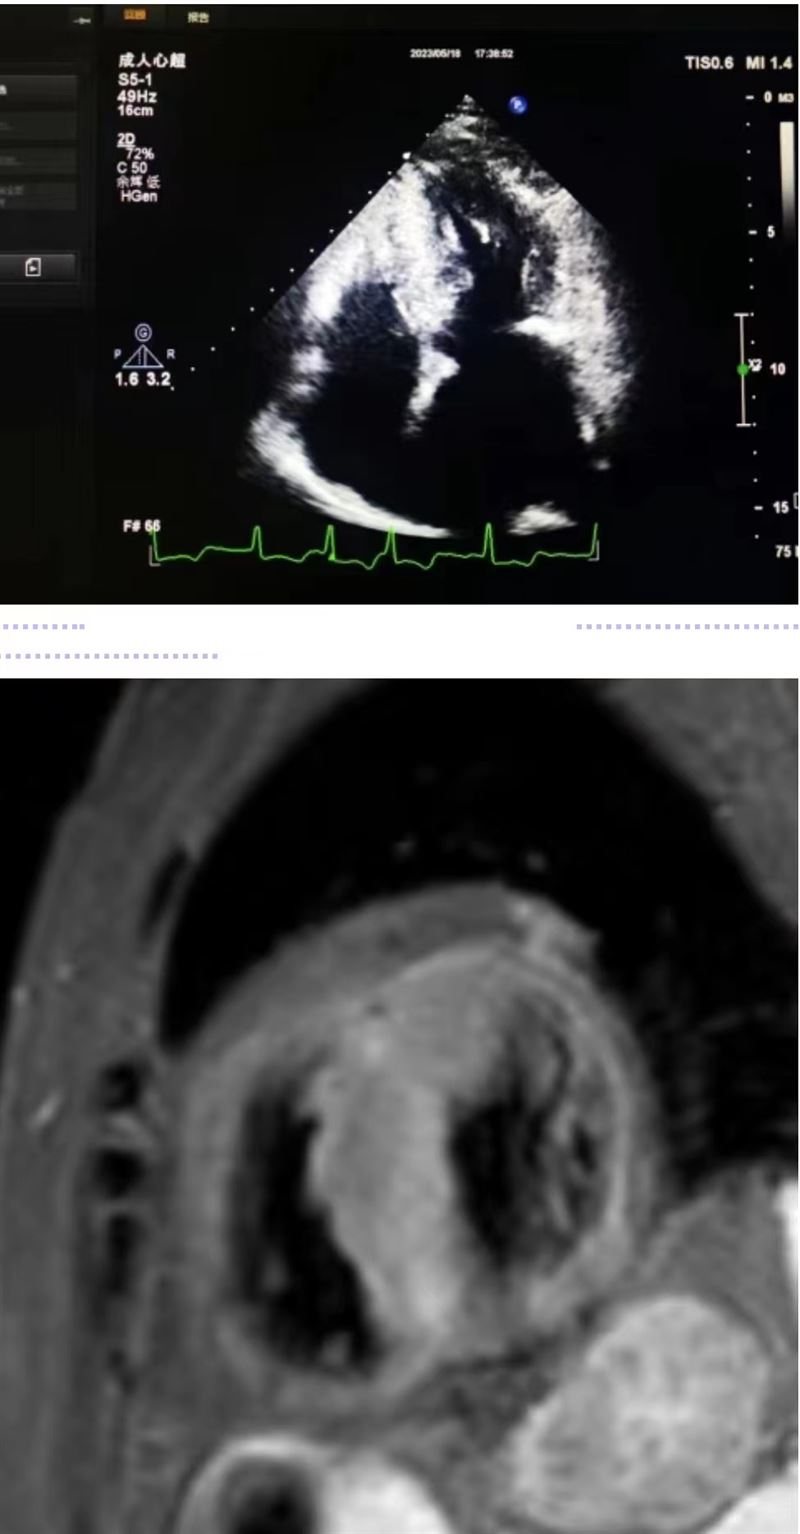

超聲科王英莉主任及心血管組賈貝主治醫(yī)師、陳輝主管護(hù)師及牛丹青護(hù)師為該患者行藥物負(fù)荷超聲心動(dòng)圖。監(jiān)護(hù)儀、急救車到位,常規(guī)經(jīng)胸超聲心動(dòng)圖提示室間隔增厚,左室流出道血流速度略增快,左心腔超聲造影,可清晰顯示室壁顯著增厚,符合肥厚型心肌病表現(xiàn),隨后又進(jìn)行了多巴酚丁胺負(fù)荷超聲心動(dòng)圖,靜息狀態(tài)下顯示左室流出道血流速度V:207cm/s,PG:17mmHg;3分鐘后心率達(dá)75次/分,左室流出道血流速度V:218cm/s,PG:19mmHg;6分鐘后心率達(dá)94次/分,左室流出道血流速度V:386cm/s,PG:60mmHg;9分鐘后達(dá)到目標(biāo)心率,左室流出道血流速度V:649cm/s,PG:169mmHg,停止用藥,藥物負(fù)荷試驗(yàn)陽性,檢查過程中患者無不適癥狀,最終診斷為隱匿性肥厚型梗阻性心肌病。